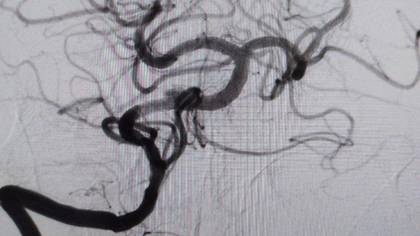

Врачи Мытищинской больницы спасли 48-летнего мужчину с редкой и опасной формой «ночного» инсульта. Об этом в среду, 19 ноября, сообщили в пресс-службе Министерства здравоохранения Московской области.

— У пациента был выявлен атеротромбоз — тромбоз на фоне атеросклеротической бляшки — основной артерии, которая обеспечивает кровоснабжение важнейших отделов головного мозга. Это очень тяжелое состояние с крайне высокой летальностью. К счастью, мы успели вовремя, и операция прошла успешно, — рассказала заведующая больницей Элеонора Тулякова.